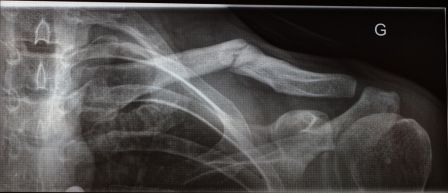

Sinon, voici les radios prises hier aux urgences :

Radio générale pour vérifier que les côtes vont bien. On voit bien la forme normale d'une clavicule sur la gauche....

La radio pour vérifier que la clavicule est cassée ou pas...pas besoin d'être médecin, ça se voit

Radio de contrôle une fois les anneaux posés. Je me demande encore s'ils sont bien utiles, pas trop de différence par rapport à la radio faite avant le pose des anneaux.

Pour info, ma clavicule une fois ressoudée en mai dernier. On voit bien que l'actuelle fracture est sur le cale de la précédente fracture, mais par contre, ça a cassé proprement sans déplacement